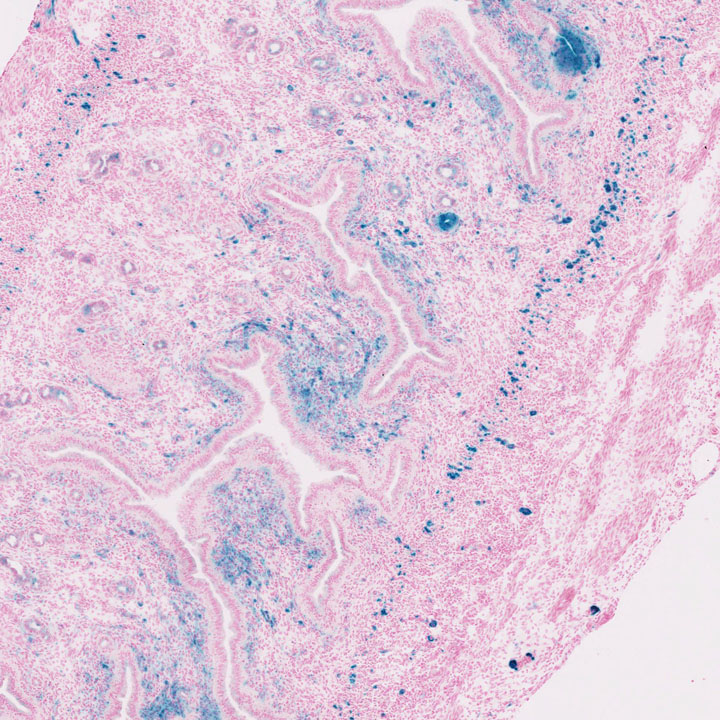

Images

Drag images to compare to others or to data in the table below. Drag corners to resize images for more detail.

Recombinase Activity